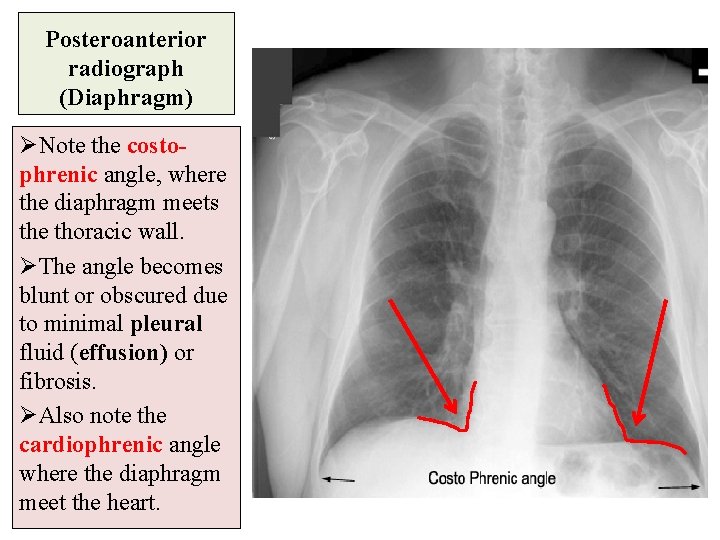

Posteroanterior radiograph (Diaphragm) Ø The diaphragm appears as a domeshaped shadow on each side; the right side is slightly higher than the left. ØBeneath the right dome is the homogeneous, dense shadow of the liver. ØBeneath the left dome a gas bubble mostly seen in the fundus of the stomach.

Posteroanterior radiograph (Diaphragm) ØNote the costo- phrenic angle, where the diaphragm meets the thoracic wall. ØThe angle becomes blunt or obscured due to minimal pleural fluid (effusion) or fibrosis. ØAlso note the cardiophrenic angle where the diaphragm meet the heart.